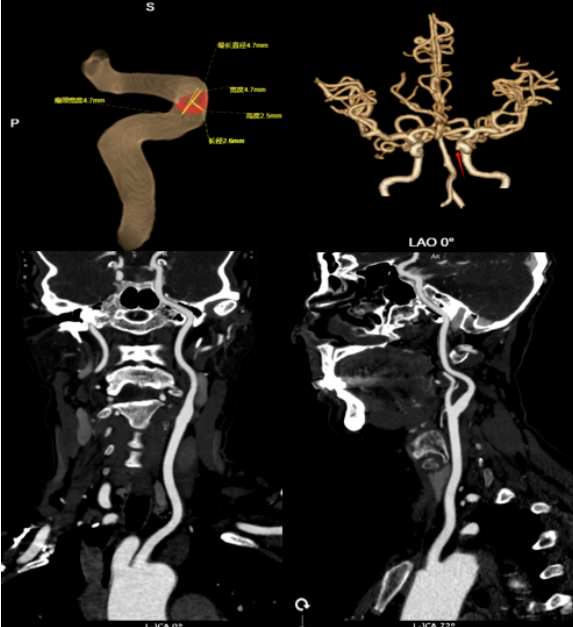

CTA结果显示:左侧颈内动脉C5段确实有一处瘤样凸起,小动脉瘤可能性大。更令人惊叹的是,中心采用的AI智能测量系统进一步精准勾勒出动脉瘤的形态、瘤颈宽度与载瘤动脉的关系,为后续治疗方案的制定提供了关键依据。

CTA(CT血管造影):通过静脉注射碘对比剂,利用CT快速扫描获取血管三维图像。其空间分辨率高,能清晰显示动脉瘤的形态、位置、与周围骨骼和脑组织的关系,是确诊和术前评估的首选。